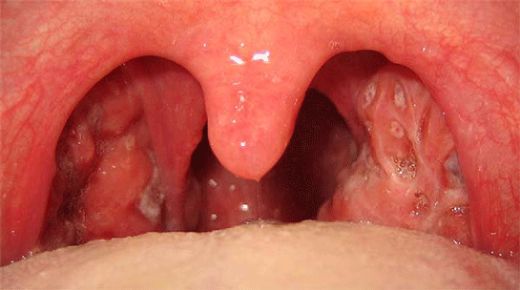

Bademcik ameliyatı, tıpta tonsillektomi olarak bilinen bir prosedürdür. Bu ameliyat, bademciklerin iltihaplanması, enfeksiyon, veya diğer sağlık sorunları nedeniyle gerekli görüldüğünde uygulanır. Ancak, her cerrahi işlemde olduğu gibi, bademcik ameliyatının da belirli riskleri ve sonrası için dikkat edilmesi gereken faktörler bulunmaktadır. Bademcik Ameliyatının Nedenleri Bademcik ameliyatı genellikle aşağıdaki nedenlerden dolayı yapılır:

Ameliyatın Riskleri Bademcik ameliyatı sırasında ve sonrasında çeşitli risklerle karşılaşılabilir. Bu riskler arasında şunlar bulunmaktadır: